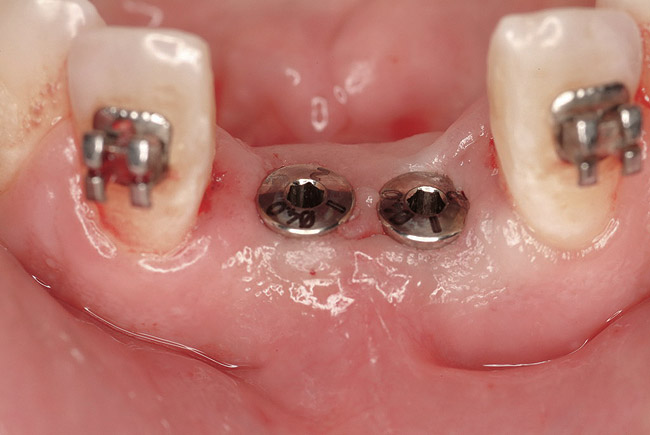

Figure 12  Flapless, computer-guided implant placement was performed. A transmucosal healing mode was chosen, with the placement of standard healing abutments.

Figure 12

Figure 23  Implant placement in the Nos. 7, 8, and 9 positions. Because the mesh did not require removal, flapless placement was possible. Note that it is visually impossible to distinguish between which side (right or left) was augmented with rhBMP-2 alone and which side was grafted with rhBMP-2 plus PLGA mesh.

Figure 23